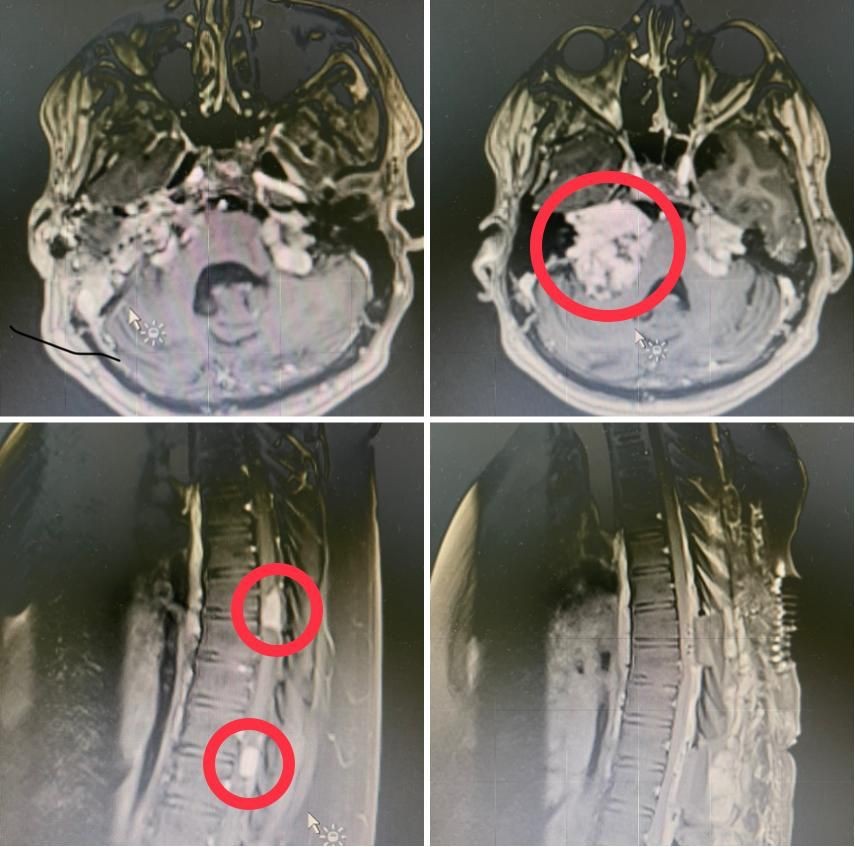

نجح فريق طبي تكاملي بمدينة الملك عبدالله الطبية بالعاصمة المقدسة عضو تجمع مكة المكرمة الصحي ممثلا بمركز العلوم العصبية من استئصال ورم ليفي عصبي ضخم في قاع الجمجمة ضاغطاً على جذع الدماغ بالإضافة إلى ورمين آخرين أحدهما سحائي والآخر ليفي ضاغطين على الحبل الشوكي لشاب في العقد الثاني في عمليه نادرة وعالية الخطورة.

واستقبلت المدينة الطبية المريض والذي كان يعاني من أورام ليفية عصبية متعددة ضاغطة على جذع المخ والنخاع الشوكي ، وقد تم محاولة علاجه عن طريق الإشعاع في أحد المستشفيات قبل عشر سنوات ومع ذلك لم ينجح العلاج الإشعاعي في التحكم في تطور المرض حيث استمرت الأورام بالزياده في الحجم مما أدى إلى عدم القدره على المشي بدون مساعدة.

في المرحله الأولى تم إزالة الورم الليفي العصبي الملاصق لجذع الدماغ تحت المراقبة العصبية وباستخدام جهاز الملاحة الجراحية والميكروسكوب الجراحي في عمليه استغرقت تسع ساعات حيث قام بإجراء التدخل الجراحي الدكتور محمد غازي عبده استشاري جراحة المخ والأعصاب والعمود الفقري  والدكتور عصام  صالح استشاري جراحات الأذن والدكتور سيد الأهل من تخدير الأعصاب والدكتور أسامة شمس من المراقبة العصبية الفسيولوجية حيث تحسنت حالة المريض بانتظار المرحلة الثانية.

حيث تم تحضير المريض لاحقا لعمل التدخل الجراحي الثاني  للورمين الضاغطين على الحبل الشوكي في تدخل  جراحي واحد وتحت المراقبة العصبية واستخدام الميكروسكوب الجراحي حيث استغرق التدخل الجراحي ست ساعات والتي أوضحت نتائجها وجود ورمين من نوعين مختلفين أحدهما سحائي والآخر ليفي

وتكللت ولله الحمد العمليات الجراحيه بالنجاح مع إزالة الأورام الضاغطة على الحبل الشوكي وجذع الدماغ  مع تحسن  قدرة المريض على المشي.